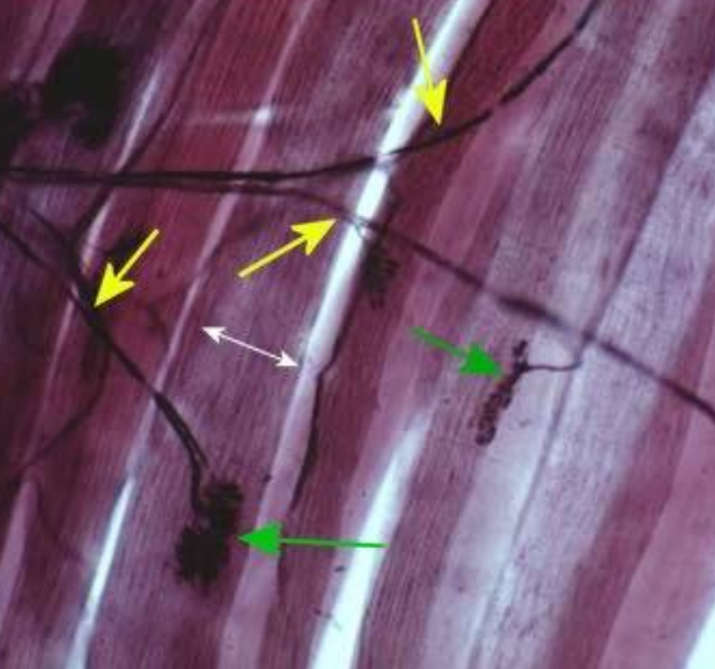

What is the pointer on?

Axon of a somatic motor neuron

What are the GREEN arrows pointing to?

Neuromuscular Junction

What are the YELLOW arrows pointing to?

Axon of a somatic motor neuron.

What is the WHITE arrow pointing to?

skeletal muscle fiber